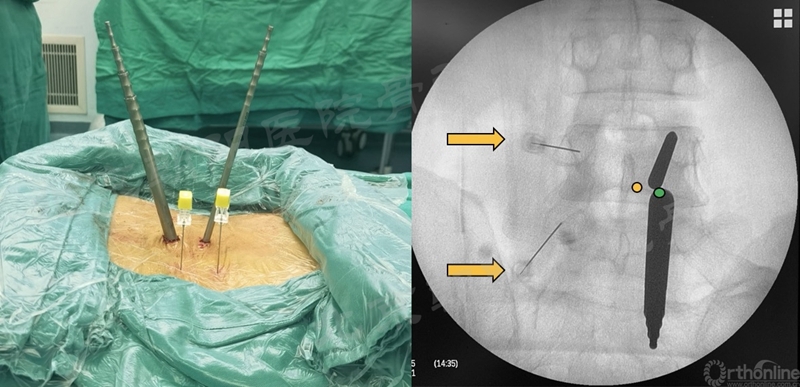

Tips-1:在对侧椎弓根投影位置临时放置2枚标记针,有助于术者空间定位,防止因长时间操作,或镜下结构辨认不清晰时失去方向,做到对侧,甚至做错节段。

2、 镜下迷失——节段错误

#14例UBE,术中迷路,L5/S1突出做到了L4/5(右侧透视图),及时转开放减压。

本例手术镜下迷失原因总结:

① 术前设计切口靠近端,本期望利于椎板钳减压椎板,弄巧成拙;

② 定位后通道方向没有记牢,操作时角度改变了;

③ 做L5/S1体位摆放应注意把上半身摇高,使L5/S1水平;

④ 透视正位应将L5/S1间隙标准化,否则定位不准;

⑤ 患者肥胖,脂肪软组织厚;

⑥ 镜下结构不对马上透视。